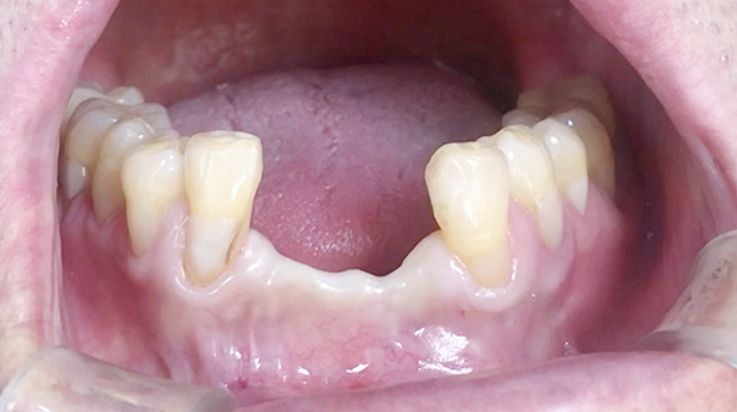

Horizontal ridge augmentation

A surgical procedure to increase the width of alveolar ridge which have been resorbed after tooth or teeth were lost